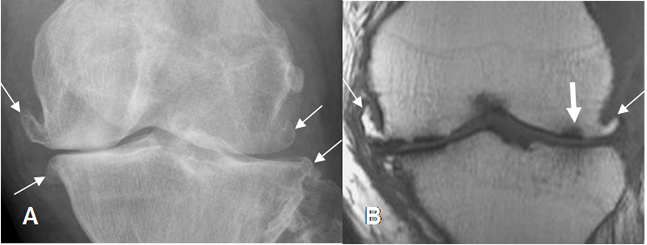

Fig 198. Artropatía degenerativa.

A: Rx AP y B: RM coronal en T1. Cambios degenerativos con formación de osteofitos (Flechas delgadas), disminución de los espacios femorotibiales, erosión de las superficies articulares y lesiones osteocondrales. (Flecha gruesa).